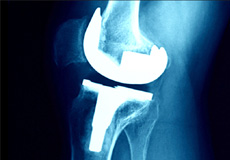

Total knee replacement, also called total knee arthroplasty, is a surgical procedure in which the worn out or damaged surfaces of the knee joint are removed and replaced with an artificial prosthesis.

Total knee replacement, also called total knee arthroplasty, is a surgical treatment for painful arthritis of the knee in which the worn-out or damaged surfaces of the knee joint are removed and replaced with an artificial prosthesis.